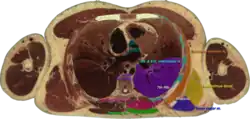

![]() Cross section #1428 of the Visible Human Male showing the structures of the triangle of auscultation | |

The triangle of auscultation is a relative thinning of the musculature of the back, situated along the medial border of the scapula which allows for improved listening to the lungs.

It has the following boundaries:

- medially, by the inferior portion of the trapezius

- inferiorly, by the latissimus dorsi

- laterally, by the medial border of the scapula

The superficial floor of the triangle is formed by the lateral portion of the erector spinae muscles. Deep to these muscles are the osseous portions of the 6th and 7th ribs and the internal and external intercostal muscles.